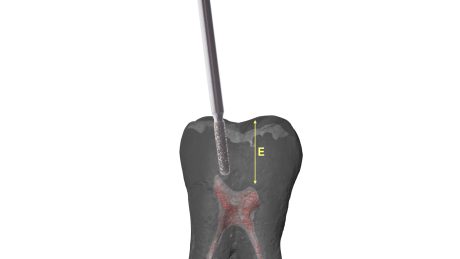

La regola dell'opalescenza e della traslucenza entra in gioco in casi di calcificazioni camerali, situazioni in cui distinguere il pavimento della camera pulpare dalla presenza di residui calcoli può risultare complesso. Iniziare a sondare con strumenti a mano o meccanici un canale prima di aver rimosso tutte le calcificazioni camerali può determinare diversi rischi: complesso inserimento degli strumenti che sarebbero anche sottoposti a un maggiore stress durante la loro attivazione, disseminazione di frammenti all’interno dei canali che potrebbero ostruirsi a diversi livelli.

In aiuto dell’operatore la differente capacità di riflettere la luce (l’utilizzo di una sorgente luminosa assieme al sistema ingrandente agevola molto nella valutazione) del pavimento rispetto al tessuto calcificato risulta un prezioso riferimento.

Il pavimento della camera pulpare si presenta sempre con un aspetto più scuro ed opaco rispetto al tessuto calcificato che tende ad essere lucido con un effetto che potremmo definire “vetrificato” (Figure 15-20).

Talvolta la differenza è evidente, in altri casi molto più sottile e quindi anche le difficoltà incontrate possono essere maggiori.

Asciugare la camera pulpare è il primo passaggio da compiere per poter visualizzare in modo netto le differenze.

A seguire l’utilizzo alternato di vari dispositivi a secco a bassi giri permette di distaccare ed eliminare i residui calcificati.